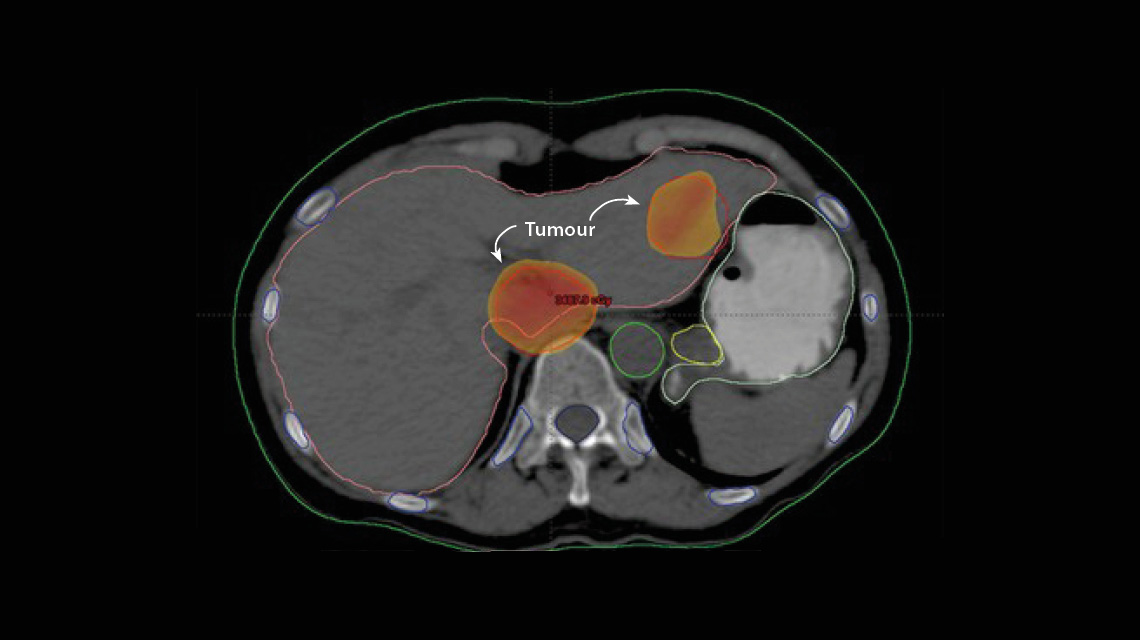

Imagen de un cáncer hepático que se tratará mediante un método avanzado de radioterapia denominado radioterapia estereotáctica corporal.(Fotografía: Instituto Nacional del Cáncer, Egipto)

La SBRT ha llevado el control y la precisión a otro nivel. La singularidad de esta técnica reside en el uso de imágenes cuatridimensionales (altura, anchura, profundidad y, en algunos casos, movimiento) para planificar y administrar la radiación que se aplica a un tumor desde distintos ángulos mediante haces muy precisos. Cada haz por separado tiene dosis de radiación más bajas, siendo así más seguro y reduciéndose el riesgo de efectos secundarios en los tejidos sanos que se encuentran en su trayectoria pero, cuando estos convergen en el tumor, exponen las células cancerosas a una dosis de radiación combinada más alta. Así pues, por lo general, se necesitan menos sesiones para tratar a un paciente de manera eficaz.

La SBRT ha mejorado drásticamente las opciones de radioterapia en los casos de cáncer hepático como el CHC, según explica el Sr. Shouman. Actualmente, el cáncer hepático es la tercera causa más frecuente de muerte por cáncer a nivel mundial. Durante a?os, la radioterapia tradicional no fue eficaz para tratar este tipo de cáncer, ya que no era posible administrar en condiciones de seguridad dosis de radiación lo suficientemente elevadas a un tumor hepático por los riesgos que ello comporta para el tejido sano circundante. Con la SBRT hasta los peque?os tumores hepáticos pueden tratarse con dosis más altas de radiación sin da?ar el tejido sano.